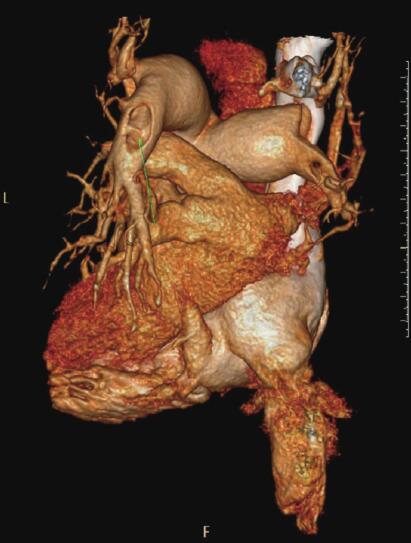

肺动脉CTA:双肺动脉干可见低密度充盈缺损,右上肺动脉未见显影,右下肺动脉、左下肺动脉可见低密度充盈缺损(图1,2)。双侧下肢静脉内可见广泛低密度充盈缺损。

图1

图2